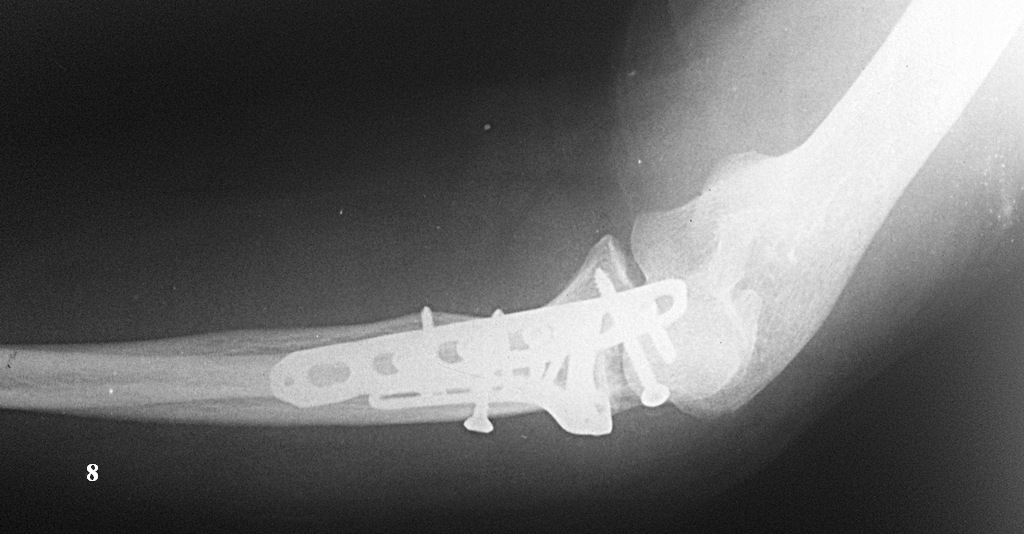

http://youtu.be/vdeYGTWrTmkНа рентгенограмме тоже вроде ничего. (рис. 7, 8).Из реабилитации порекомендовали заниматься с первого дня движениями в суставе (пронация/супинация, сгибание/разгибание), выполнять несложную домашнюю работу. Видео объма движения на 7-е сутки после операции по ссылке: http://youtu.be/KyPAUmEIhs4